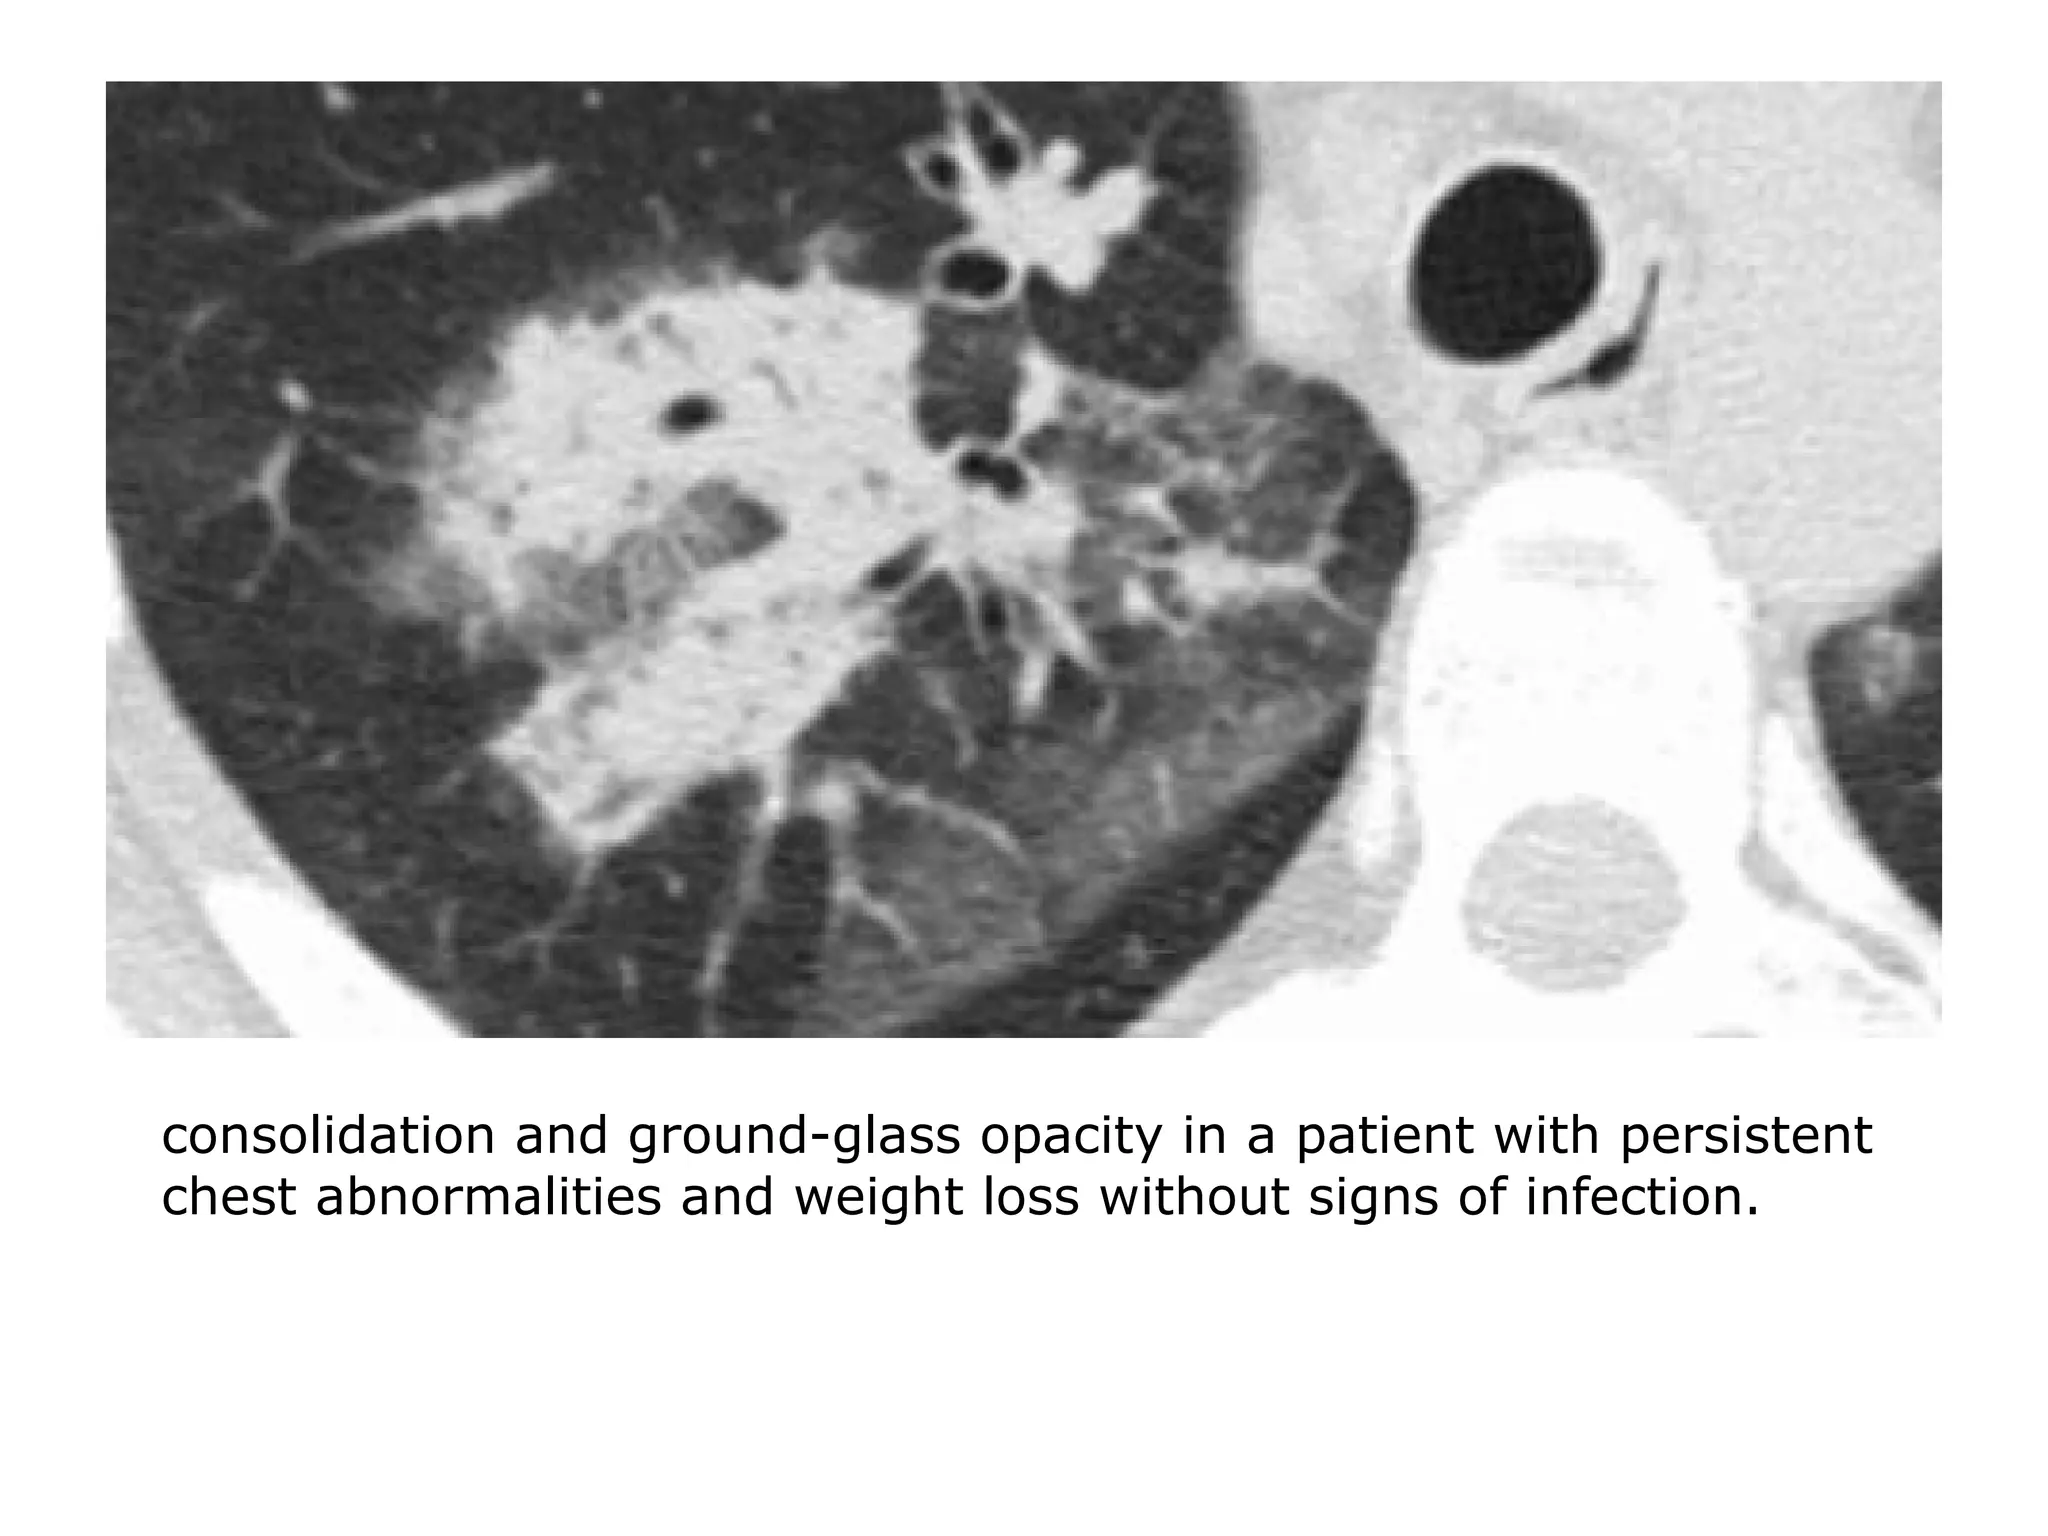

consolidation and ground-glass opacity in a patient with persistent

chest abnormalities and weight loss without signs of infection.

• Ground-glass opacity is nonspecific, but a highly significant

finding since 60-80% of patients with ground-glass opacity

on HRCT have an active and potentially treatable lung

disease.

• In the other 20-40% of the cases the lung disease is not

treatable and the ground-glass pattern is the result of

fibrosis.

• In those cases there are usually associated HRCT findings of

fibrosis, such as traction bronchiectasis and honeycombing.